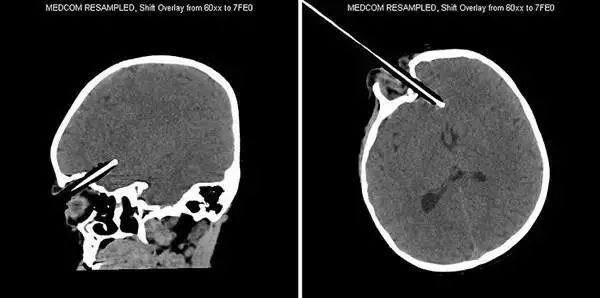

6、这把*首匕**扎入了一名仅有10岁大的阿富汗小男孩的头部,经过手术之后被取出,并在医院接受后续治疗。

7、这名不幸的患者被一根撬棍刺穿头部。